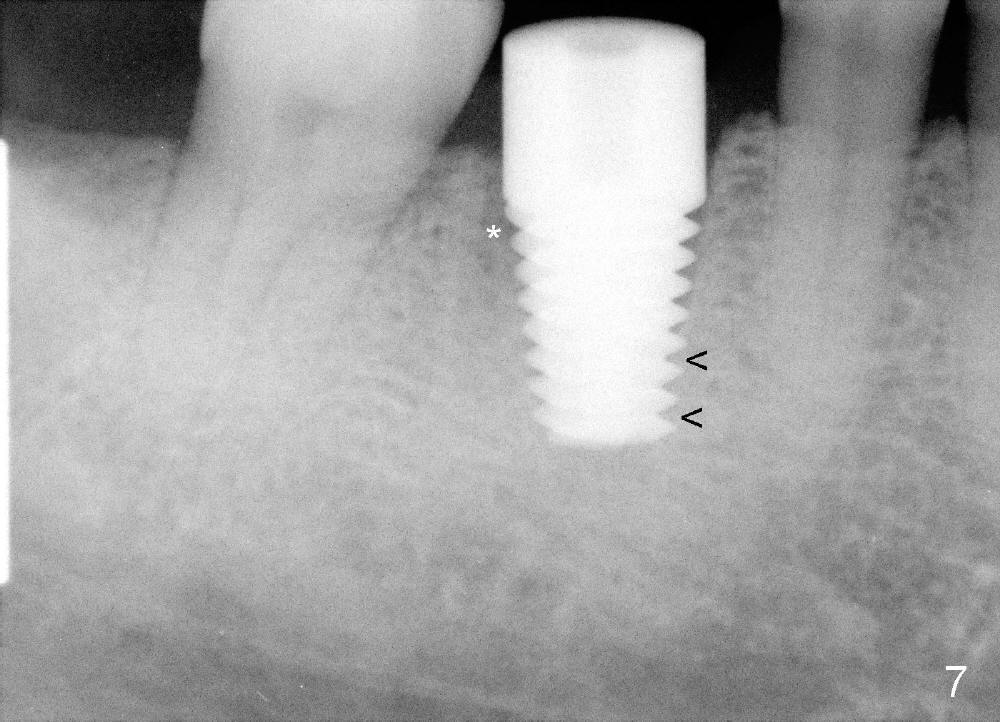

A 47-year-old man has had perio infection in the lower right 1st molar twice (Fig.1,2). Buccal and lingual furca pockets are ~ 9 mm. Following extraction and sectioning the septum, the osteotomy is initiated with a 2 mm pilot drill (Fig.3). Although the drill deviates into the mesial socket, the coronal end is controlled more or less in the middle of the edentulous area (compare white and red lines). Ideally the axis of the osteotomy (Fig.4 red line) should be parallel to that of the 2nd molar and perpendicular to the curve of Spree. The coronal end of the 3.5 mm reamer (Fig.5) and of the 7x17 mm tap (Fig.6 T) remains in the center of the edentulous space. The apical threads of the tap are engaged into the bone for stability (Fig.6 <). When 7x17 mm implant is placed with > 60 Ncm, the mesial socket is obliterated while the density of the distal one increases because of autogenous bone grafting (Fig.7*).

The distal socket is closed completely with suture, whereas the mesiobuccal space is partially closed with collagen gauze and suture (Fig.8 *). The wound is then covered by perio dressing. The gingiva heals around the implant 18 days postop (Fig.9). Three months postop, the implant is stable. The mesial upper portion of the threads appears to have better contact with the bone (Fig.10 <, as compared to Fig.7); the density of the distal socket seems to increase (*). There is no buccal plate atrophy (Fig.11 ^). Supragingival margin is designed for the crown to prevent periimplantitis (Fig.12)